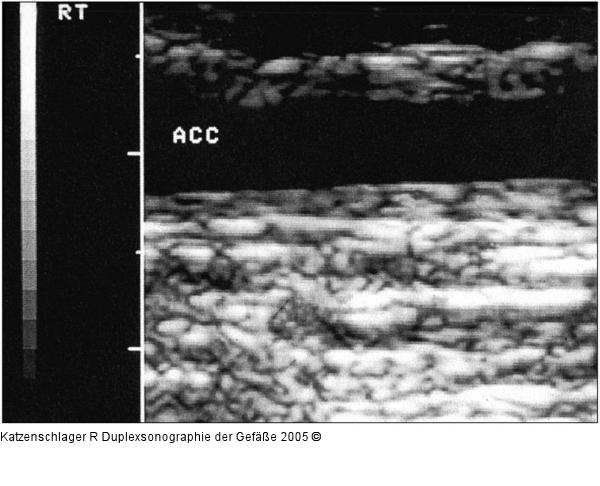

Abbildung 7: Duplexsonographie - Intima-Media - Karotis

Verdickung der Intima-Media in der A. carotis communis bei Arteriitis |